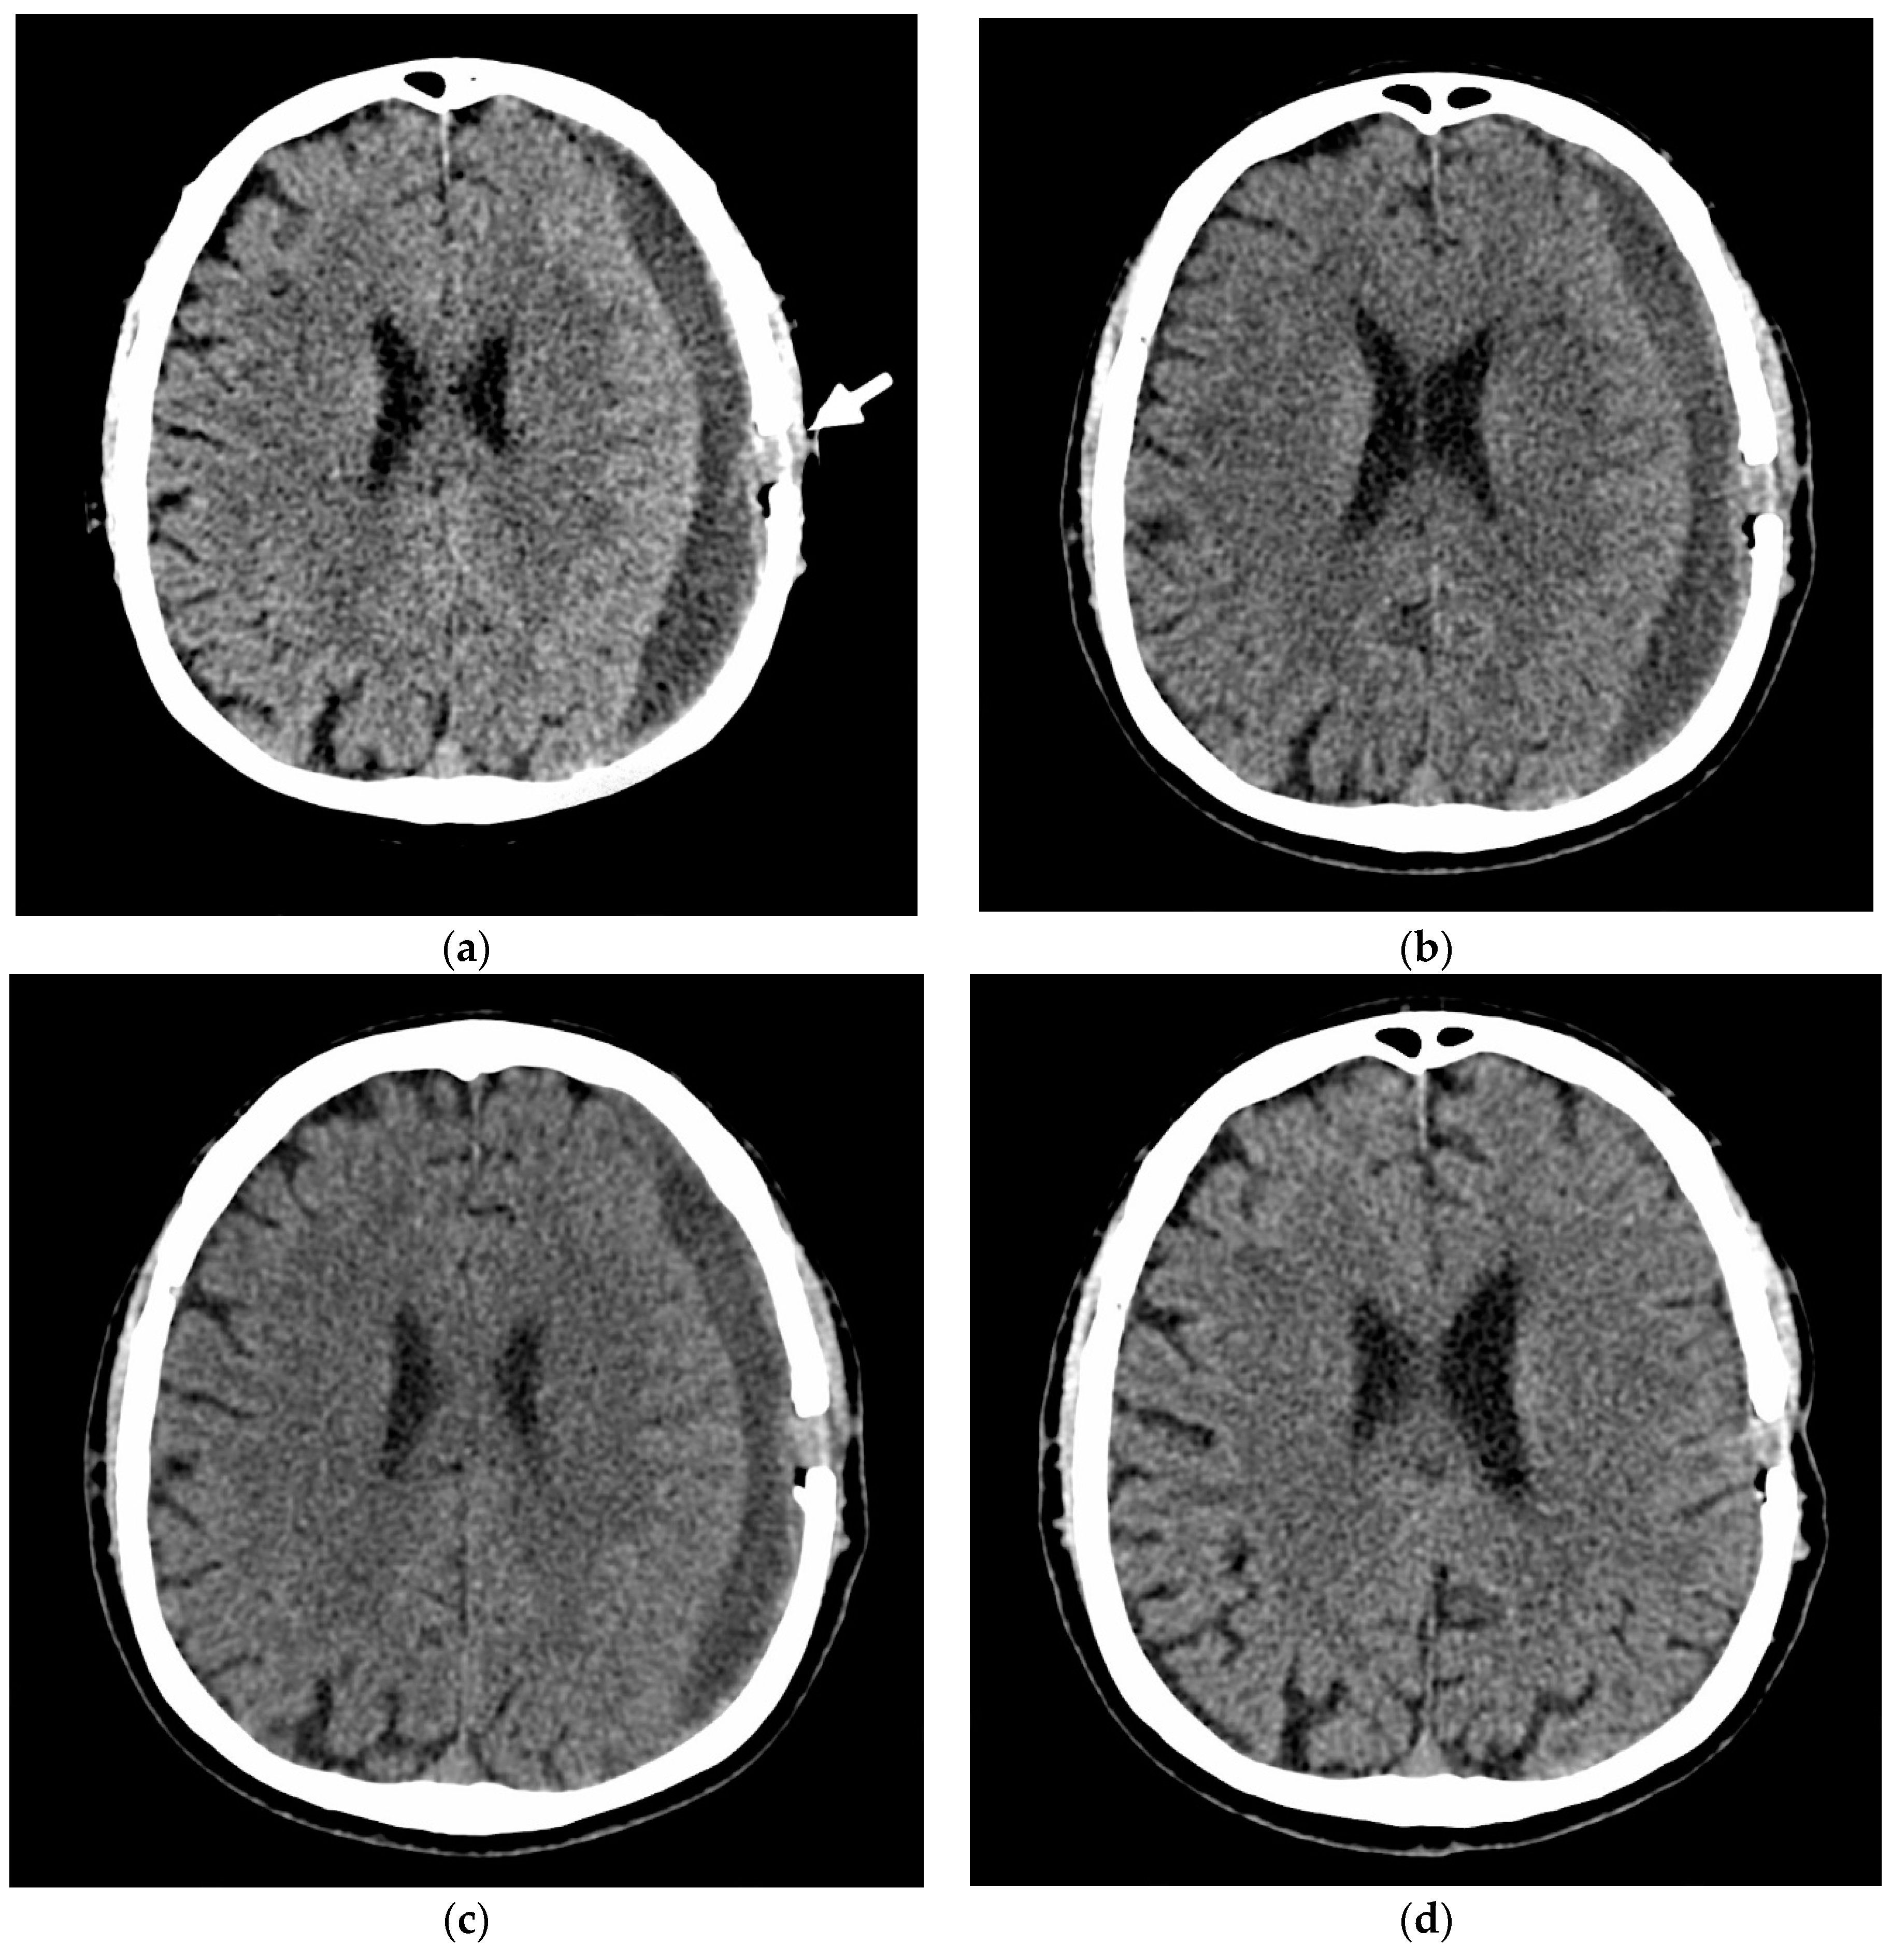

- A 70-year-old patient with left-handed CSDH and a midline shift of 12 mm, motor aphasia, and right-hand hemiparesis.

- A 42-year-old patient with bilateral CSDH that progressively increased during 1.5 months from 54 mL to 69 mL on the right-hand side and from 68 mL to 83 mL on the left-hand side, causing significant compression of both hemispheres and neurological deterioration.

- An 89-year-old patient with bilateral CSDH (no midline shift). There was no apparent connection with an antecedent head injury. However, the patient’s relatives reported that the patient did periodically fall. At the time of admission, the patient presented tetraparesis and a decreased level of consciousness.